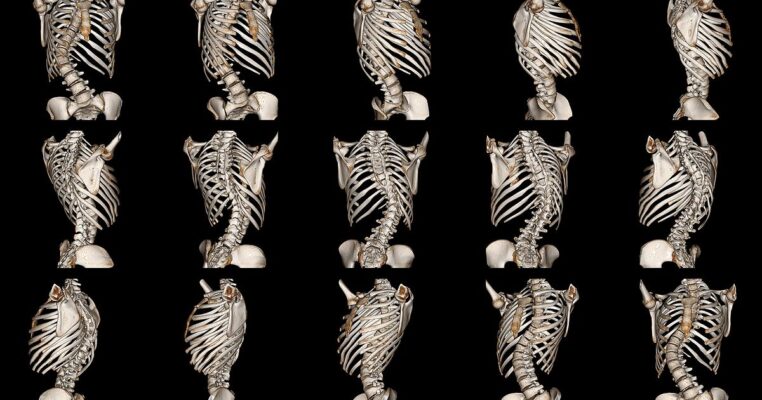

Escoliosis Costilla Sobresaliente: Cómo abordar el problema de las costillas sobresalientes debido a la escoliosis y opciones de tratamiento

Scoliosis, a condition characterized by an abnormal curvature of the spine, can often lead to [...]

Escoliosis de la Caja Torácica Desigual: Manejo y tratamiento de la deformación de la caja torácica causada por la escoliosis

Uneven Rib Cage Scoliosis is a comprehensive guide that delves into the management and treatment [...]